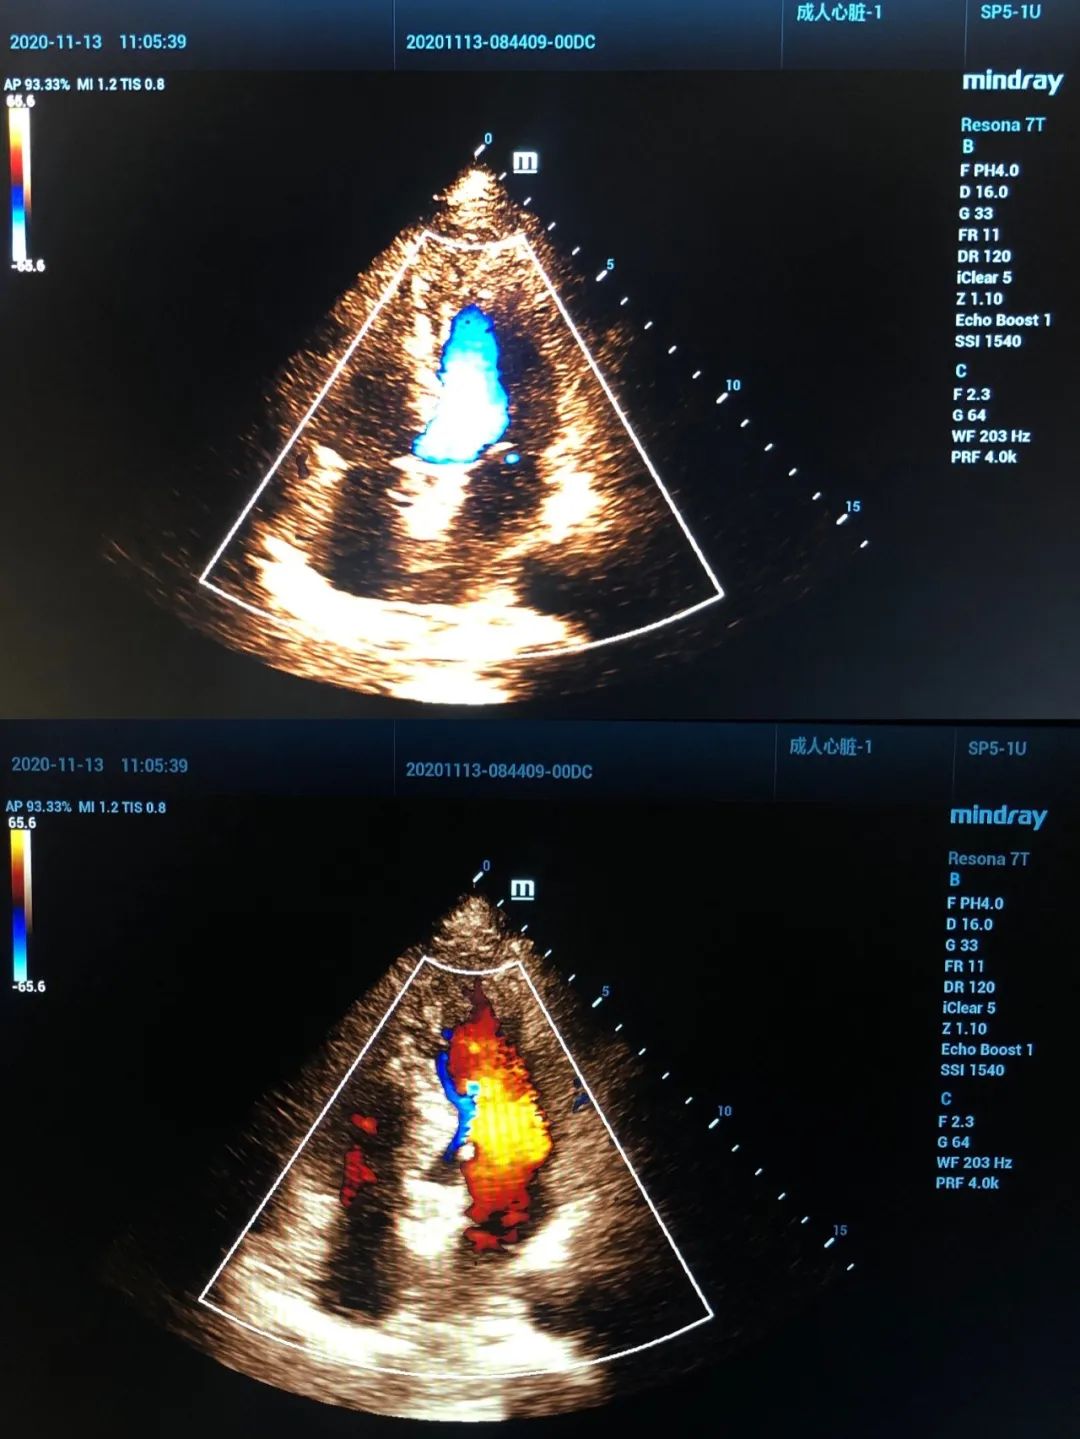

强大的心脏彩超多普勒

依靠高性能彩色多普勒超声功能,作用于心脏大血管系统,可发现相应心脏当中的缺损部位及心脏瓣膜的扩张、狭窄、病变,以及相应大血管的动脉粥样硬化,还有相应血栓等情况,具有多角度、多方位观察功能,且显像清晰,诊断准确率高。